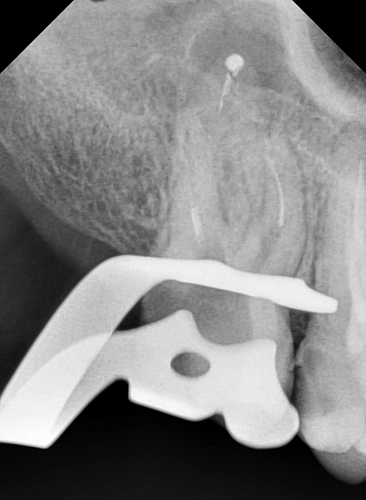

На следующих снимках видно, что отломок инструмента был успешно извлечён. Все каналы были пройдены, механически обработаны под микроскопом и запломбированы.

Работа врача -стоматолога -микроскописта Овчинниковой М.И